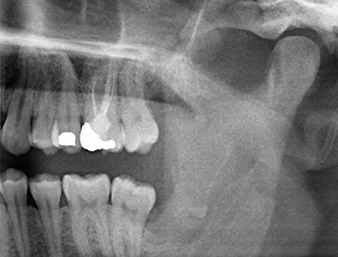

Der Wurzelrest regio 38 zeigte bereits in der Panoramaschichtaufnahme eine enge Lagebeziehung zum Nervus alveolaris inferior. (Abb. 1)

Abb. 1: Panoramaschicht-Aufnahme 6 Monate nach Osteotomie Zahn 38: Radix relicta liegt nahe dem Nervus alveolaris inferior.